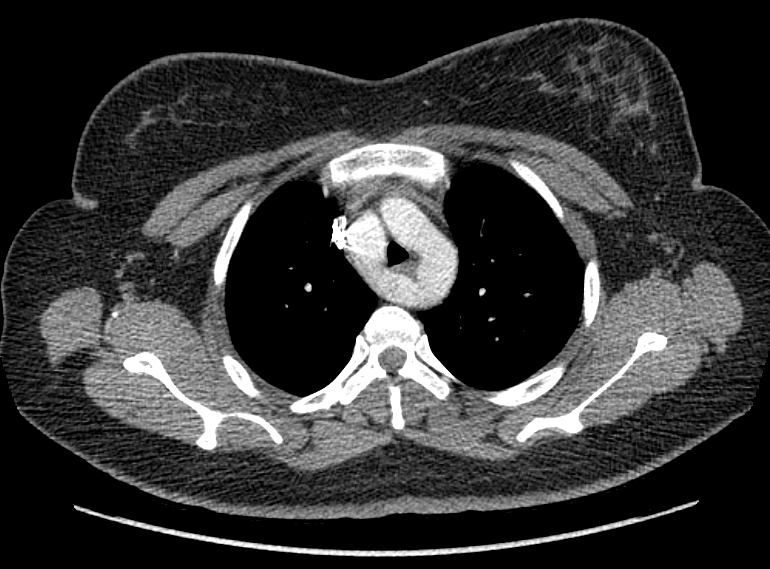

F/34

°Ç°­°ËÁø»ó ½ÃÇàÇÑ Chest PA »ó mediastinal widening ¼Ò°ßÀ¸·Î further evaluation À§ÇØ ³»¿øÇÔ.

Áõ»óÈ£¼Ò ¾øÀ¸¸ç ½Åü°ËÁø»ó ƯÀÌ¼Ò°ß ¾øÀ½.